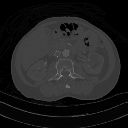

- A choice of filters can generally be selected to enhance either soft tissue features in the image or bone detail. Indeed, the image can be post-processed using a different filter after the scan has been completed if needed. Images can be generated to enhance bone detail or display subtle low contrast masses without the need to re-scan the patient. The filter choice therefore has a major impact on image quality. The two most common filters used in X-ray CT are those due to Ramachandran & Lakshminarayana (commonly called the Ram-Lak) and Shepp & Logan. Viewed in spatial frequency space, the former is essentially a ramp filter with a cut off frequency and the latter combines a smoothing filter with the ramp to attenuate high frequency noise. The ramp filter compensates for the artefacts introduced by the simple back projection process but does not compensate for the increasing noise content of the data with increasing frequency. Images of an axial tomogram reconstructed with a soft tissue and with a bone algorithm can be seen in Figure 7.14.

![]() |

- Examples of image display manipulation are shown in the two figures above. In Figure 7.15.2, the same image of a slice through a patient's liver is displayed using a relatively narrow window (high contrast) and also with a wide window. The image with the narrower window appears noisier, but this is merely a reflection of the fact that the gray scale is spread over a narrow range of CT-numbers.

- Figure 7.15.3 illustrates the use of a relatively narrow window to highlight pathology in the lungs.